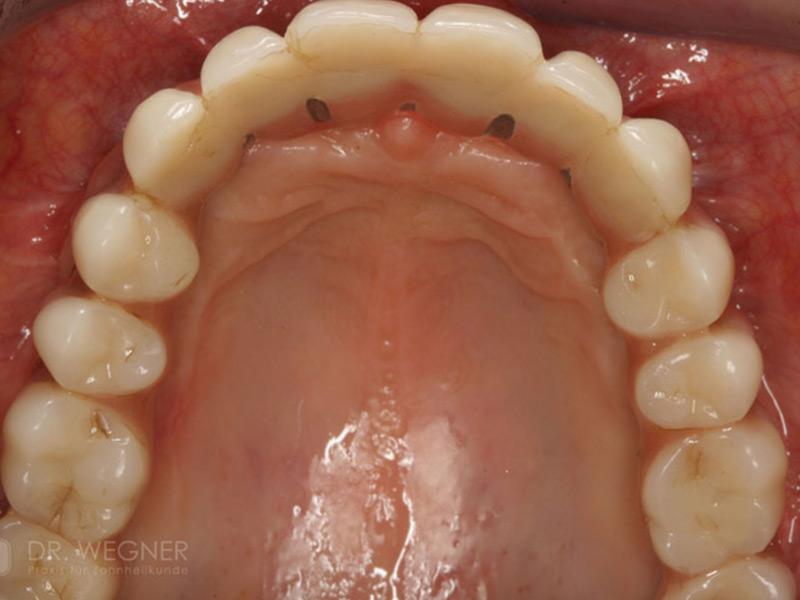

Zahnimplantate werden anhand von moderner virtueller 3D-Planung passgenau geplant und inseriert. Der Vorteil von Implantaten besteht darin, dass festsitzender ästhetischer Zahnersatz auch in solchen Fällen realisiert werden kann, in denen sonst nur herausnehmbare Prothesen möglich wären. Zudem ist im Gegensatz zur Brückenprothetik kein Beschleifen der Nachbarzähne notwendig.

Unter dentalen Implantaten versteht man im allgemeinen eine Schraube, die dort, wo ein oder mehrere Zähne verloren gegangen sind, in den Kieferknochen "eingepflanzt" wird. Diese Therapieform der Implantologie hat sich in den letzten Jahren zu einem alltäglichen Therapieverfahren in der Zahnheilkunde entwickelt. Wissenschaftliche Untersuchungen zeigen hierfür eine Erfolgsquote von i. d. R. 80-98 % über 10 Jahre. Verglichen mit anderen zahnärztlichen Maßnahmen gibt es nahezu keine andere Therapie mit derart guten Erfolgsaussichten. Auch eine Verbesserung der Lebensqualität wird durch implantatgetragenen Zahnersatz laut klinischer Studien erreicht.

Mittlerweile hat sich die Implantologie zu einem alltäglichen Therapieverfahren mit sehr guten Erfolgsaussichten in der Zahnheilkunde entwickelt. Bei guter Mundhygiene und regelmäßigen Kontrolluntersuchungen können fachmännisch gesetzte Zahnimplantate ein Leben lang halten.